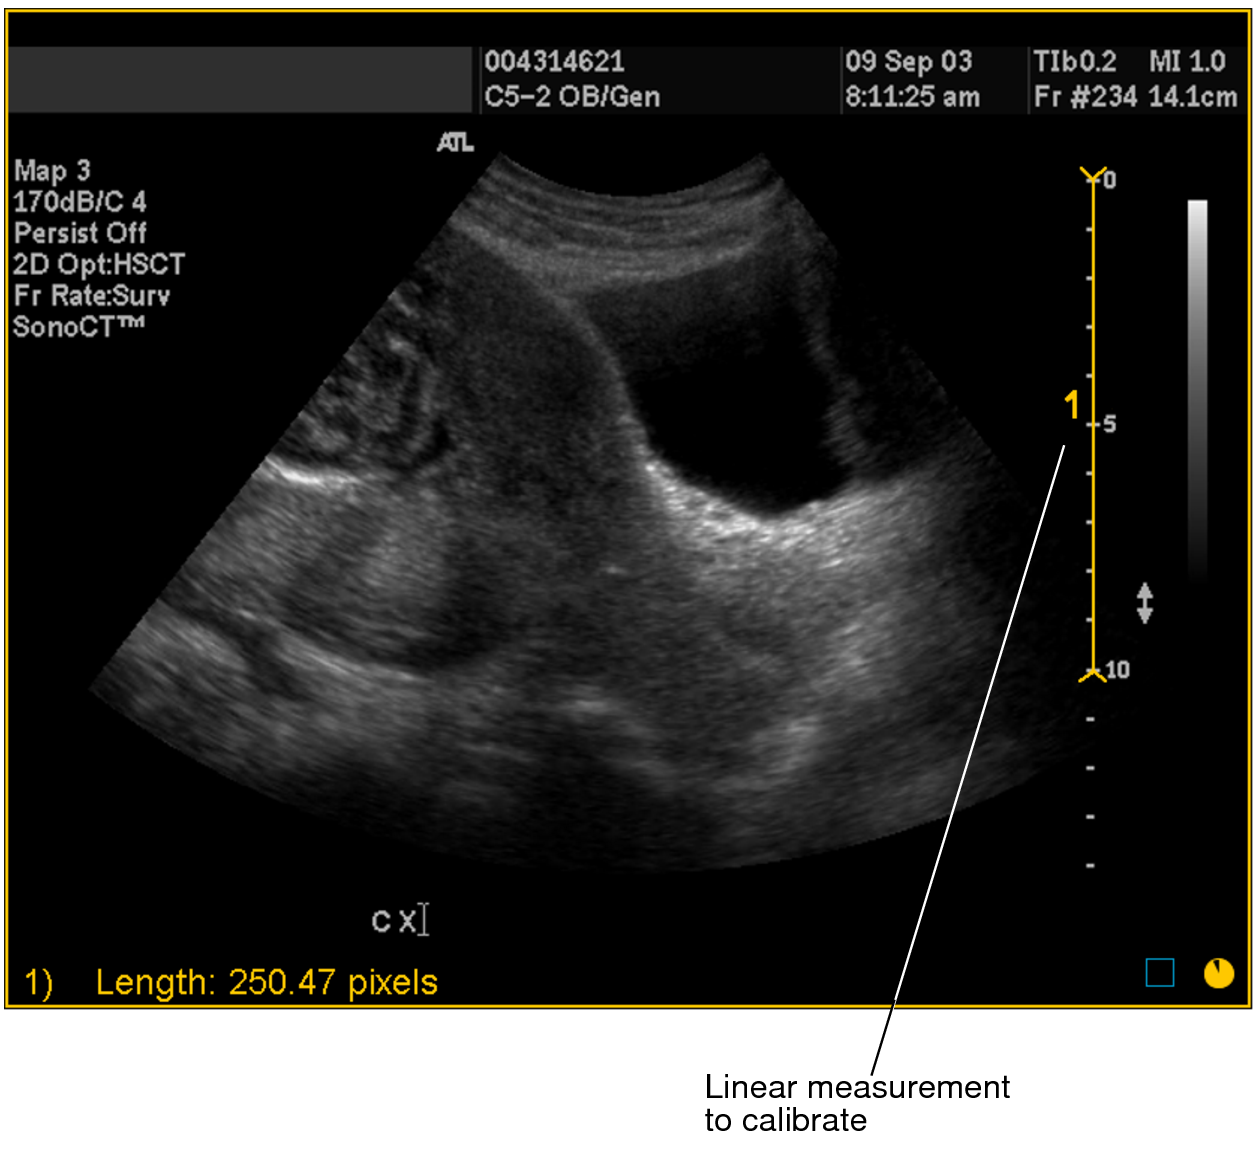

- Draw the line whose length you will use to define the

ratio of pixels-to-centimeters. You should draw this line on a scale

or other element of the image whose length in centimeters is accurately

known. To draw the line, click the Linear Measurement tool

. -

Click at the starting point of your measurement and drag. Release the mouse button at the end of your measurement.

A numbered measurement line appears, and the corresponding length appears in the bottom left corner of the viewport. Notice that the length is displayed in pixels.